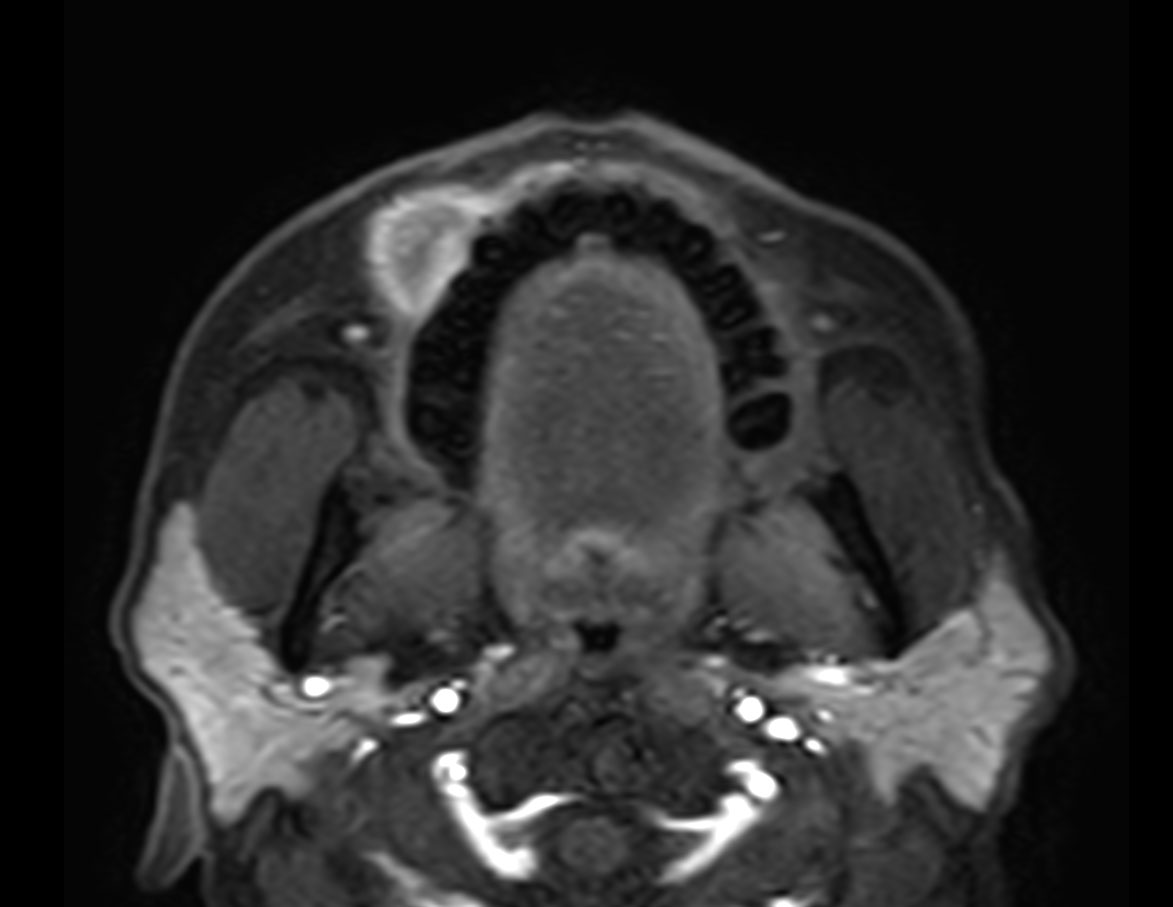

Axial T1w TSE FatSat (post gado)